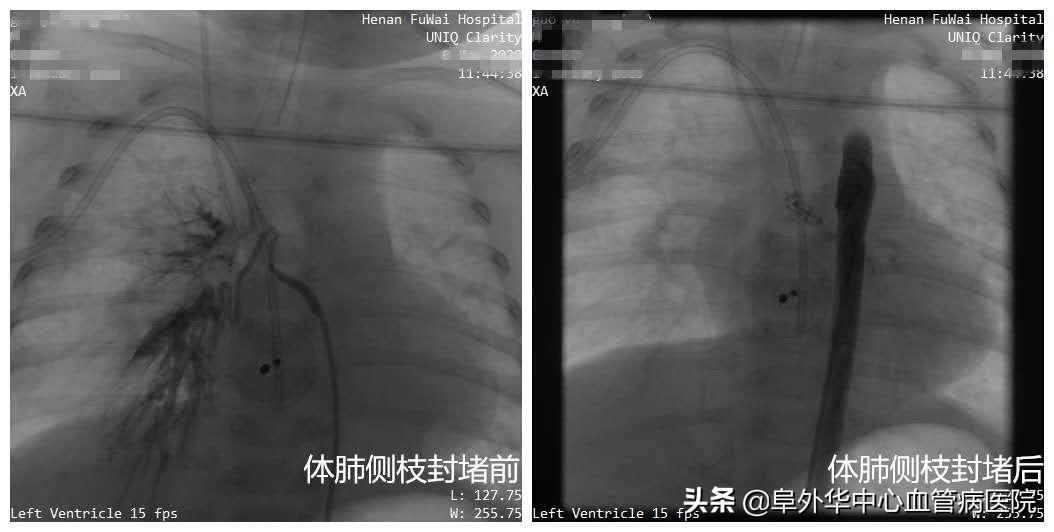

范太兵教授像福尔摩斯一样,大胆推测、抽丝剥茧,逐步逼近事情的真相。进一步掌握证据后,专家们心里有了底。无影灯下,范太兵教授、宋书波博士等专家开始实施手术。在先进的杂交手术室,进行术中动脉造影,打入造影剂后果然发现,小患者有粗大体肺侧枝形成,直径足有4毫米以上!正是这根本来不该存在的血管,导致血液灌注肺部,它才是引起肺炎和气喘的真正元凶,而室间隔缺损(中轻度)和动脉导管未闭不会造成这样的结果。

紧接着,专家们一鼓作气,为孩子实施了“房间隔缺损微创封堵+体肺侧枝封堵术”。整个手术过程,仅有1.5个小时。范太兵教授等专家不但抽丝剥茧找到“真凶”,而且用微创手术代替开胸手术,不但大大降低创伤,而且为患者节省了大量费用。